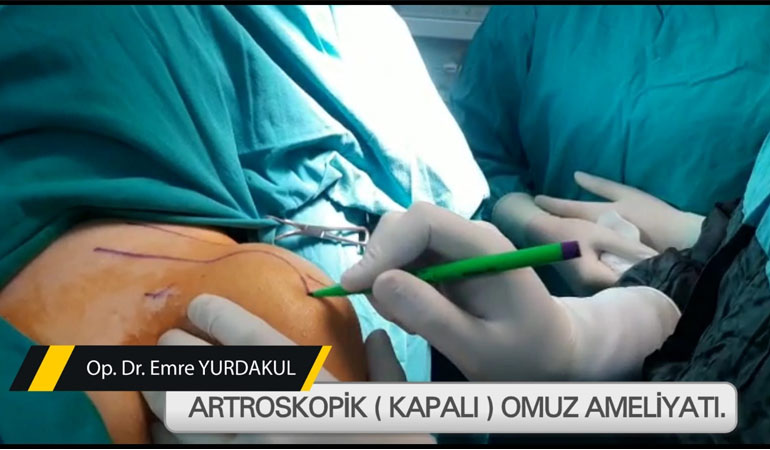

OP. DR. EMRE YURDAKUL: ORTOPEDİDE AMERİKA’YLA EŞ DEĞER DURUMDAYIZ

Sağlık turizminde son yıllarda ülke olarak ulaştığımız seviye, büyük dikkat çekerken Kayseri System Hospital doktorlarından Op. D […]